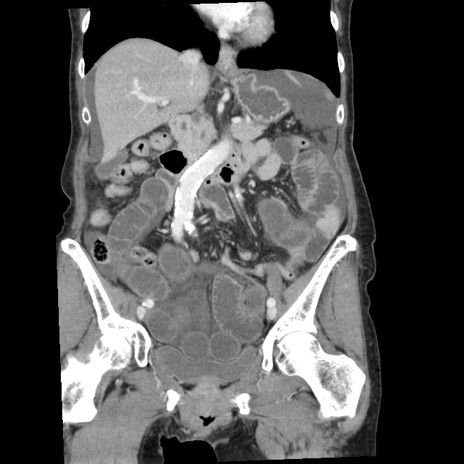

横断像